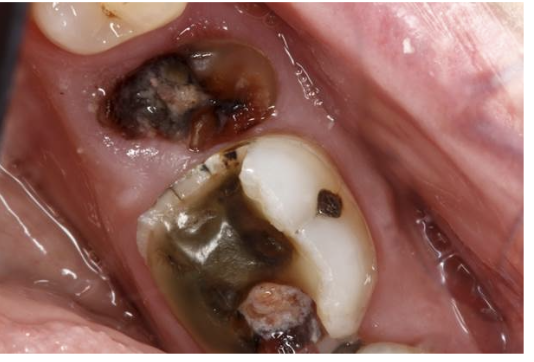

In the photo below we see an example of a patient. The patient desires a treatment pant for an RCT, buildup and crown on #30, and an extraction on tooth #29.

Which of the following are things to consider prior to this treatment in terms of treatment planning a bridge from #28-#30?

a) discuss with the patient the possible consequences if #29 is not replaced once it is extracted

b) taking the necessary radiographs to assess the area

c) an assessment of the patients occlusion

d) taking a thorough medical history

e) all answers are correct

A